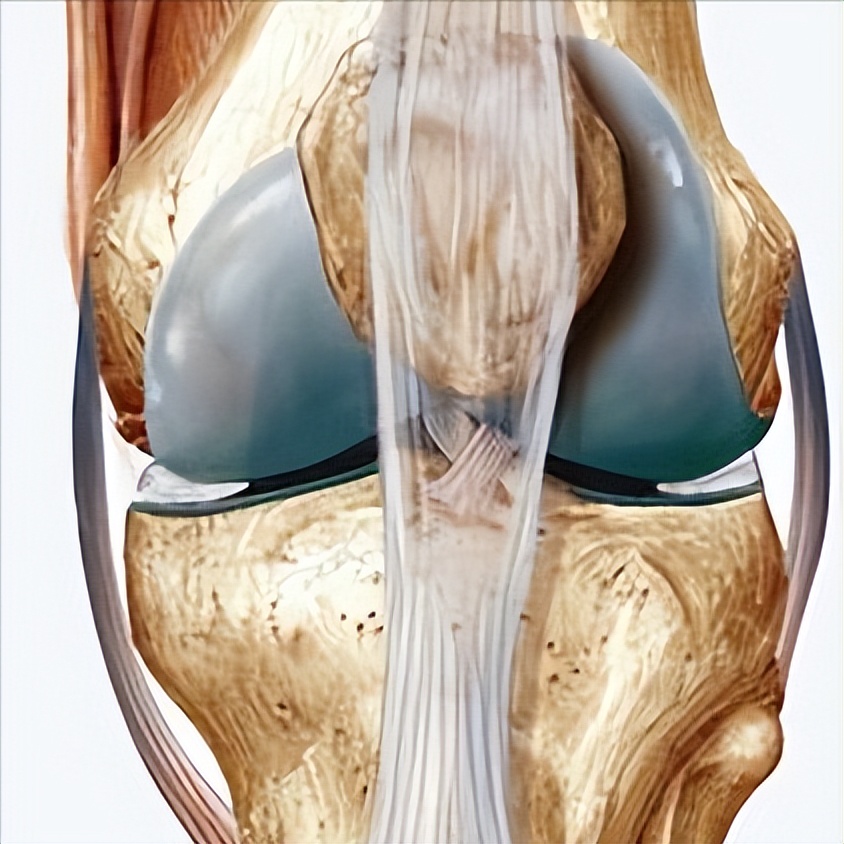

半月板损伤

修复半月板是一种纤维软骨组织,起减震器的作用,具有稳定和润滑关节、本体感觉和负荷分配等功能。 负重或外伤时突然的扭转运动可能会导致半月板损伤,从而导致疼痛、肿胀和活动困难等症状。

由于其缺乏血管组织,传统的药理学和外科治疗不能导致健康组织的再生。 采用压痛点注射PRP的方法慢性半月板损伤,发现治疗后1月、2月、3月的膝关节Lysholm评分分别均有明显改善,治疗后3月VAS明显下降。

且膝关节McMurray试验及半月板损伤程度较治疗前改善,以上发现说明PRP注射治疗慢性半月板损伤可缓解疼痛、改善体征,并促进半月板愈合 。也有其他研究也支持PRP治疗半月板损伤可有较好的临床疗效。

Kaminski等对比关节镜下修复半月板撕裂后修复部位注射PRP及生理盐水的疗效,结果表明PRP在半月板修复中促进了半月板愈合并改善了关节功能。

此外, 还有大量研究也表明关节镜下半月板修复联合PRP治疗半月板损伤可有效缓解患者症状、改善关节功能、促进半月板修复并改善预后 。而Yang等的研究认为PRP对半月板损伤术后患者的功能情况和半月板愈合率并没有明显改善。